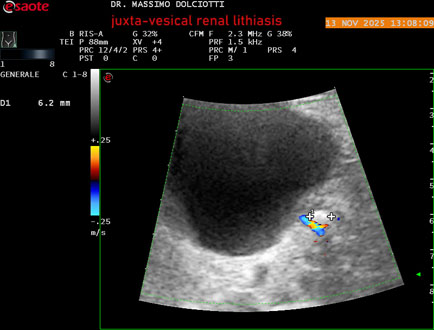

Ecografia del: 13/11/2025

Strumento: Esaote MyLab Eight

Sonda: Convex Multifrequenza 1-8 MHz

Età Paziente: M 59 anni

Motivazione dell'esame: dolori al basso addome ed al fianco sinistro, comparsi la notte precedente.

Commento all'esame: le immagini ed il video documentano al rene sinistro, idronefrosi di 1°-2° grado, con presenza di immagine iperecogena, con cono d'ombra posteriore, allo sbocco dell'uretere sinistro, in sede iuxta-vescicale, delle dimensioni di 6,2 mm, con segno del Twinkling Artifact (o segno di Arlecchino), da ricondurre a litiasi.

Conclusioni: litiasi renale sinistra iuxta-vescicale (left juxta-vesical renal lithiasis).